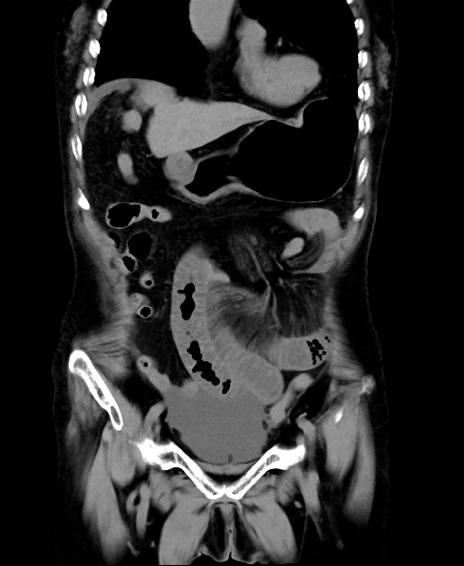

症例40(冠状断像)他院1日前

【症例】90歳代女性

【主訴】腹痛・嘔吐

【現病歴】 食欲低下、嘔吐があり昨日他院受診。肺炎と診断され入院となる。入院後より腹部全体に圧痛あり。胃管留置され経過みていたが、症状持続するため、

当院転院となる。

【既往歴】胸椎圧迫骨折、胆石症

【身体所見】腹部:中央に激痛あり、圧痛あり、反跳痛不明

【データ】WBC 17100、CRP 18.82

他院CT

横断像

矢状断像